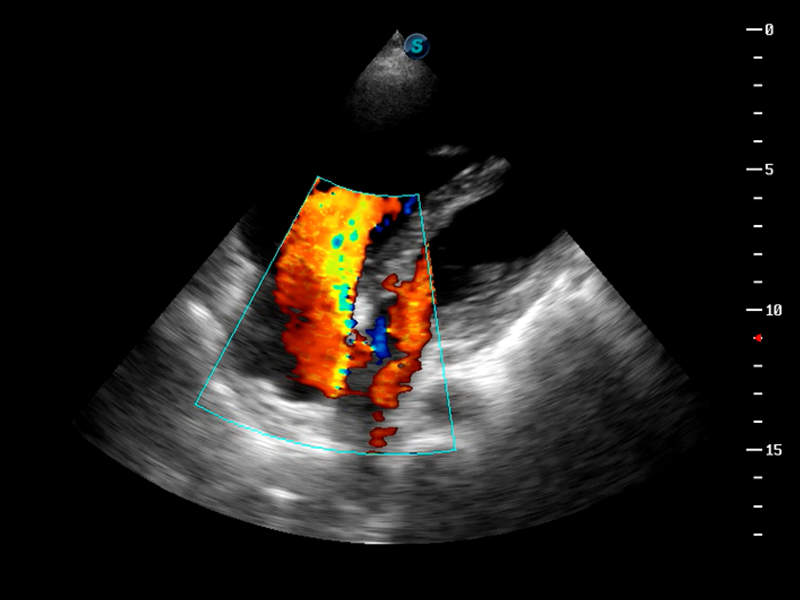

S9

S9便携式彩色多普勒超声诊断仪是1xBET研发的高端便携彩超设备,外观设计新颖、产品性能卓越。S9在便携超声领域采用了突破传统的触摸屏交互设计,并以先进的软件硬件技术和设计理念,为您带来清晰的图像质量、稳定的工作性能和便捷的操作体验。